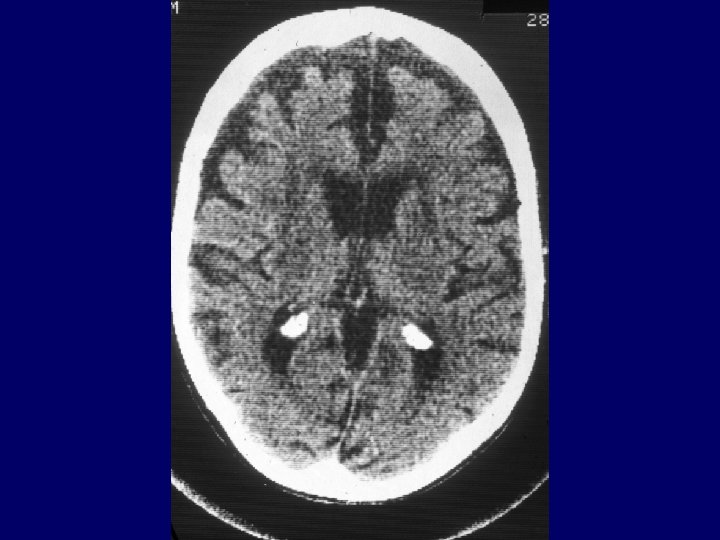

Brain CT hypodense lesions related to the spongy leukoencephalopathy Brain MRI data is sparse Skeletal Muscle Biopsy shows in almost all patients with KSS typical ragged-red fibers Heart muscle has no ragged-red fibers There is no histopathological difference between KSS and PEO in muscle biopsy specimens

Mitochondrial Dysfunction Serum lactate level pre and post exercise Brain CT or MRI for spongy leukoencephalopathy Skeletal muscle biopsy for histochemistry, electromicroscopy for detection of raggedred fibers Skeletal muscle biopsy or blood for examination for mt. DNA deletions